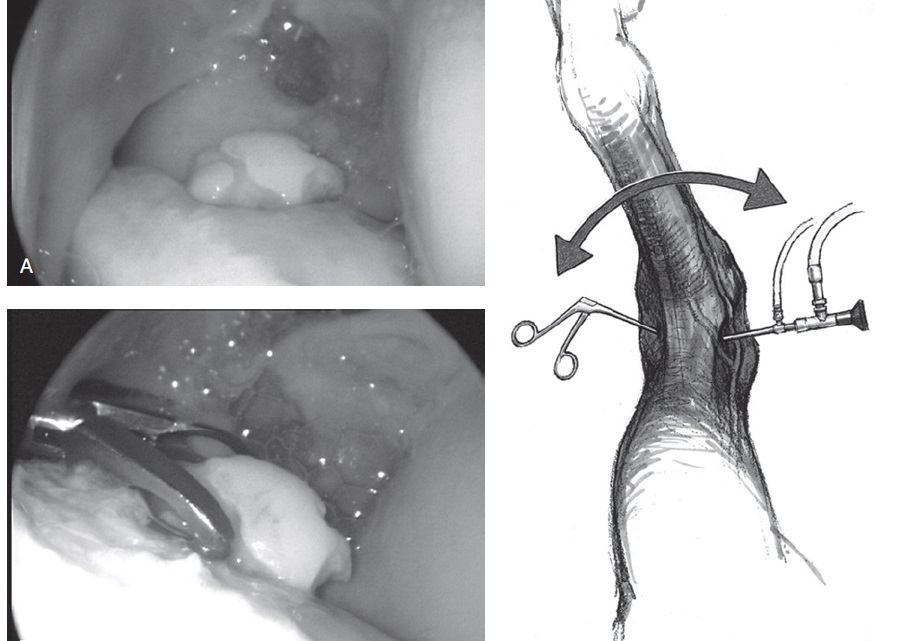

How would you approach the fragment from previous image (extensive chronic fracture of the proximal plantar aspect of the medial trochlear ridge (MTR))?

Extensive fractures of the proximal plantar aspect ofthe MTR have significant synovial and joint capsuleattachment (Figure 34.7). Dissection of the soft tissuesmay require arthroscopic scissors, curved fixed‐bladescalpels, periosteal elevators, and synovial resectors. Removal of the free fracture fragmentmay require forceps with aggressive teeth, includinginsertion of Ochsner forceps or towel clamps.Rarely, large fractures will need to be divided using anosteotome, prior to removal in pieces.